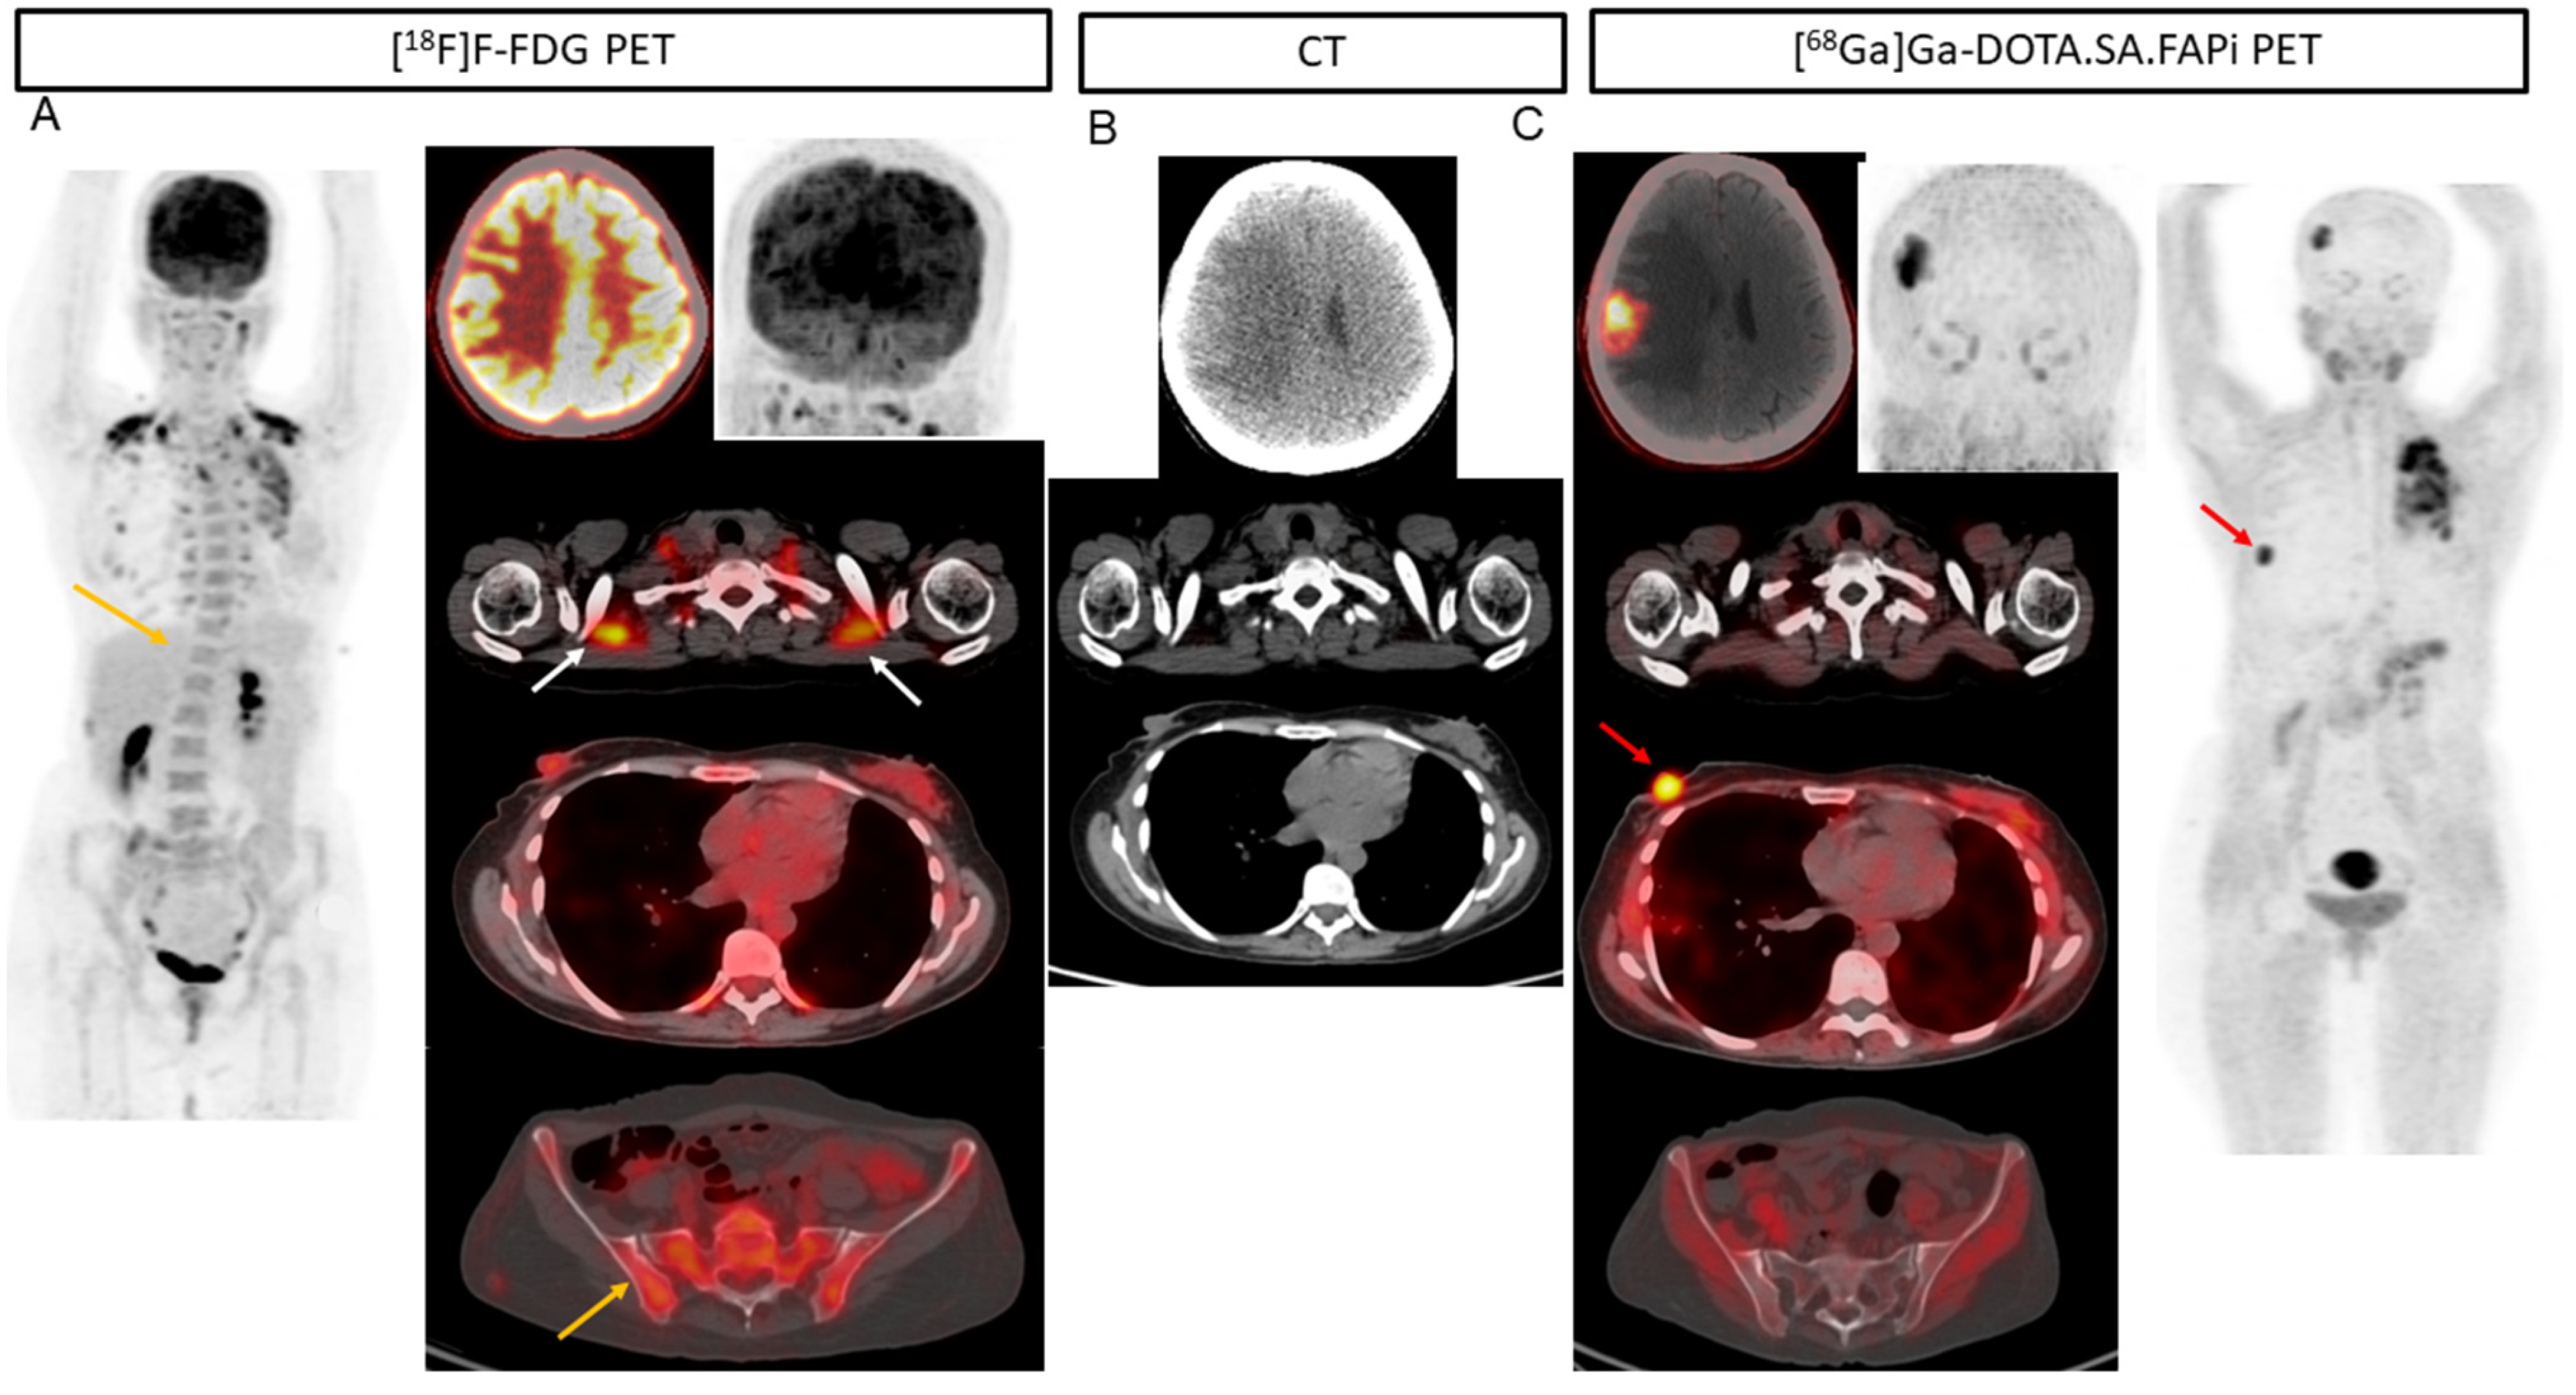

Among the 17 patients with liver metastases [68Ga]Ga-DOTA.SA.FAPi and CT accurately detected all 88 lesions (100%), but the accuracy decreased to 96.5% (85/88). The superiority of [68Ga]Ga-DOTA.SA.FAPi over [18F]F-FDG is portrayed in Figure 2. Due to increased physiological hepatic FDG uptake, the liver lesion (A) is masked in the [18F]F-FDG PET/CT as compared to the [68Ga]Ga-DOTA.SA.FAPi PET/CT (minimal FAPi physiological hepatic uptake) (C) and corresponding lesion on CT (B). [68Ga]Ga-DOTA.SA.FAPi had higher detectability of pleural metastases than [18F]F-FDG (15 vs. 13). [68Ga]Ga-DOTA.SA.FAPi definitely changed the imaging technique for brain metastases wherein [68Ga]Ga-DOTA.SA.FAPi accurately detected all 42 brain metastases, whereas a drastically low number of 25 were detected on [18F]F-FDG (sensitivity 100% vs. 59.5%, p < 0.0001) (Table 1) (Figure 4 and Figure 5).

(A) 37-year-old patient with infiltrating ductal carcinoma underwent chemotherapy, Herceptin treatment, gamma knife for brain metastases, lapatinib, and capecitabine oral chemotherapy. A heterogeneous lesion measuring 1.7 × 1.4 cm was seen in the right parietal lobe associated with grade II perifocal vasogenic edema (B). (A) Due to the physiological uptake of FDG in the brain, lesions are not well demarcated (A). On [68Ga]Ga-DOTA.SA.FAPi PET scan, brain metastasis is appreciated in the MIP image itself (C). Brown fat uptake is seen on [18F]F-FDG ((A), white arrows), but no such findings were noted on [68Ga]Ga-DOTA.SA.FAPi PET scan (C). High-intensity uptake on [68Ga]Ga-DOTA.SA.FAPi in the right areola region corresponds to the mass in CT scan (B), but minimal radiotracer uptake on [18F]F-FDG PET scan (A). Diffuse non-specific bone marrow uptake was appreciated on [18F]F-FDG MIP (A) and transverse section ((A), yellow arrow) in the axial skeleton that was negative on CT (A,C) and [68Ga]Ga-DOTA.SA.FAPi (C) PET scans. [68Ga]Ga-DOTA.SA.FAPi clearly detected both primary and brain lesions on MIP itself (C).

Figure 5.

In a 54-year-old patient with bilateral carcinoma breast, the post lumpectomy of the right breast tumor and left radical mastectomy the histopathology revealed invasive ductal carcinoma (ER-/PR and HER2+). Multiple isodense lesions were noted in the right parietal and left occipital lobes (B), with surrounding edema. [18F]F-FDG PET/CT (A) underestimated the number of lesions as compared to [68Ga]Ga-DOTA.SA.FAPi PET/CT (C), as only one lesion was visualized on [18F]F-FDG PET/CT brain MIP images.

Interestingly, there was no significant difference in the SULpeak and average values in brain metastases, but remarkably high TBR values were observed on [68Ga]Ga-DOTA.SA.FAPi compared to that of [18F]F-FDG PET. [68Ga]Ga-DOTA.SA.FAPi imaging showed 10 brain metastases in one patient, while [18F]F-FDG showed only four lesions due to high background activity (Figure 1).